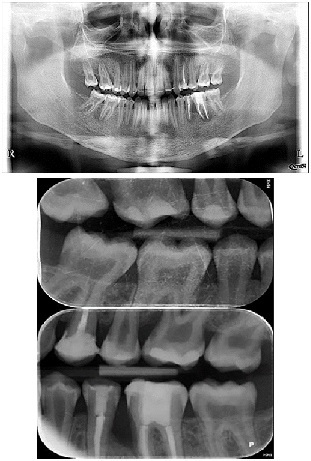

Periapical radiography (phosphorus number 2 plaque and X-MIND® Unity; Acteon) and cone-beam computed tomography (X-MIND® 3D; Acteon) (80 × 80, 150 Micron) were performed and showed periapical lesions on teeth 14, 15, 16, 24, 25, 26, 35, 36, and 46, as well as advanced endo-perio lesions on teeth 26 and 16. orthopantomogram (X-MIND® 3D; Acteon) and bitewings (phosphorus number 2 plaque and X-MIND® Unity; Acteon) also showed wide pulp chambers and roots canals. Figure 1, Figure 2

Figure 1.1 and 2 show a wide pulp chamber, root canals, and several restorations.

Figure 2.2. 3, 4, and 5 show periapical lesions on teeth 15, 16, 24, 25, 26, 35, 36, and 46.